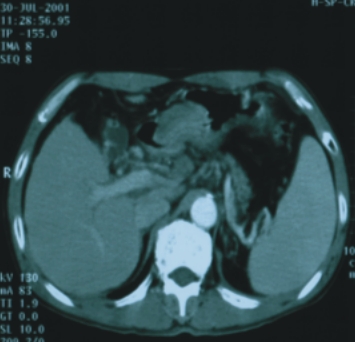

56歲/男性 (肝癌合併後腹腔淋巴腺轉移) |

74歲/男性 (直腸癌合併後腹腔淋巴腺轉移) |

||

| 90/5/2

(治療前) |

90/6/30(治療後) |

90/8/16(治療前) |

90/12/21(治療後) |